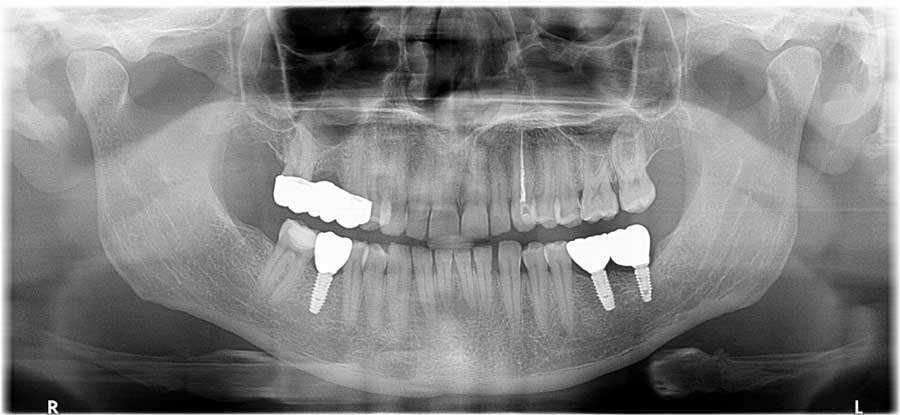

Житель Таллинна Максим (33) в 2019 году обратился в клинику Implanttihoito, чтобы поставить пломбу на зуб. «Однако мне сказали, что все плохо, что зуб надо вырывать и ставить вместо него имплант, — рассказывает мужчина. – Потом ситуация повторилась и с другими зубами. В итоге мне поставили три импланта и мост. Все это лечение обошлось мне в 5000 евро. Бонусом шли боль, осложнения, вызов скорой, капельницы, непрекращающееся кровотечение из просверленной десны, абсцесс и три месяца на кашах. Врач из другой клиники, куда я обратился, мне сказал, что нужно все сносить и заново ставить импланты». Главврач Implanttihoito отказался дать комментарии.

Оглядываясь назад, Максим говорит, что, видимо, в клинике Implanttihoito все это – удаление зубов, которые еще можно лечить, и активная продажа имплантов — поставлено на поток.

«Так как они специализируются на имплантах, то, похоже, говорят всем пациентам, что лечить нельзя, надо удалять и ставить имплант, — говорит он. – Но тогда я этого не знал и просто поверил доктору в белом халате».

За первым имплантом последовали и второй, и третий. И тоже, по словам мужчины, под тем соусом, что лечить эти зубы уже никак, только удалять. Доктора тем временем постоянно менялись: Максимом занимались то Дмитрий, то Максим, то Семен, то Иван, то Светлана. При этом на сайте клиники в разделе «Врачи» указаны только два доктора: Семен и Светлана. Дмитрий находится в разделе «Главврач». В списке персонала нет ни Максима, ни Константина, хотя в карте визитов указано, что Максима принимал некий Константин, однако по факту доктора звали Иван.